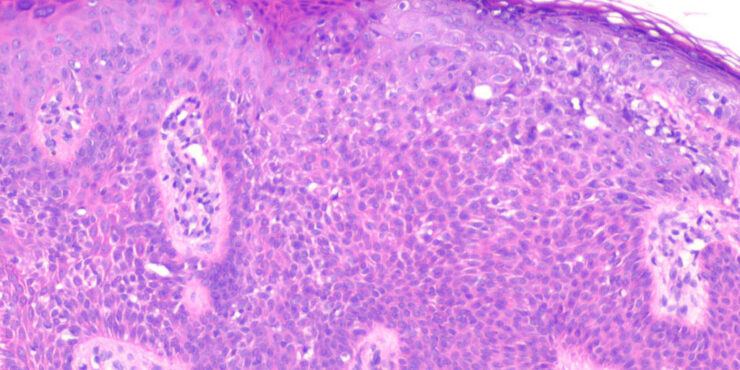

Poroma=شزن=تورم بسبب إفراز غدي POROMA The term poroma refers to a group of rare cutaneous appendage tumors composed of cells (cuticular and poroid cells) similar to those of the acrosyringium. Poromas are traditionally subcategorized histopathologically based on their location in relation to the epidermis into three main variants; namely, hidroacanthoma simplex, eccrine poroma, and […]